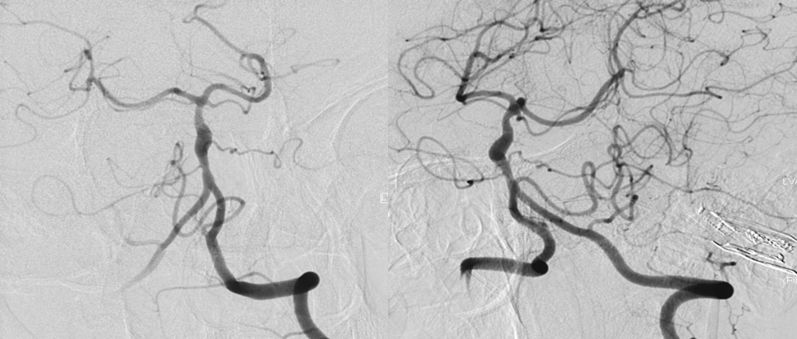

治疗过程简述

1、患者全身麻醉,右侧股动脉穿刺置入8F动脉鞘,5F中间导管携带6F长鞘超选入左侧椎动脉,行造影及三维旋转寻找最佳工作角度(图8)。

图8

2、调整至合适的工作角度后,撤出5F中间导管,将5F Navien 通过6F长鞘置入左侧V3段。路图引导下由2 m Synchro-14微导丝将T-track支架微导管超选进左侧大脑后动脉P2段(图9)。

图9

3、多个投射角度辅助下,将一枚3x35 mm的Tubridge支架经T-track支架微导管缓慢释放(图10)。

图10

4、支架完全释放后造影可见支架完全覆盖动脉瘤,贴壁良好,载瘤动脉及支架覆盖的双侧AICA及右侧椎动脉通畅(图11)。

图11